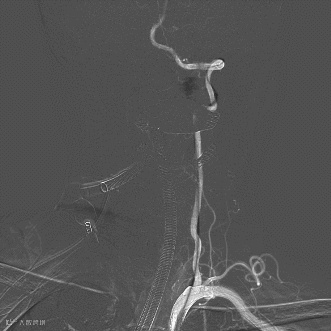

患者取仰卧位,全麻下右侧股动脉穿刺置入8F血管鞘,全身肝素化。5F单弯在泥鳅导丝引导下行全脑血管造影,可见基底动脉尖动脉瘤,左椎优势供血伴起始处迂曲,左侧非胚胎型大脑后动脉(图3,4)。

图3

图4